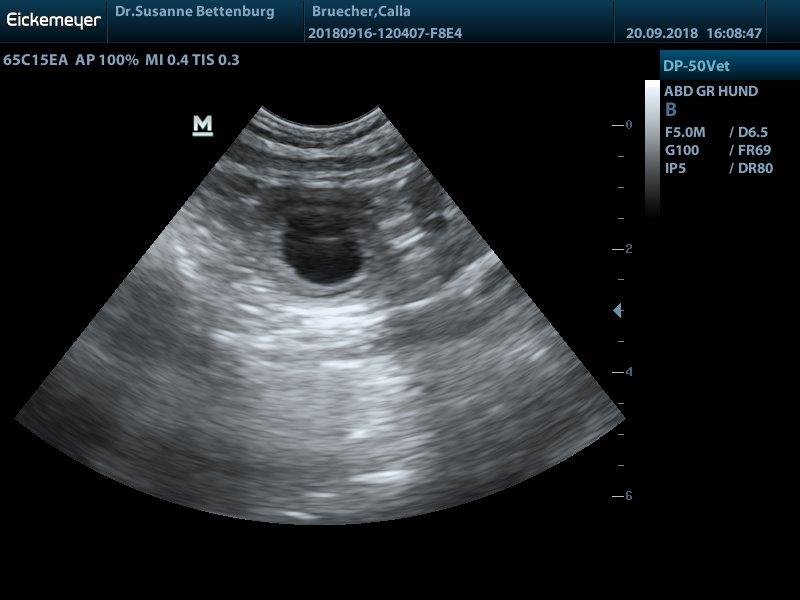

Juhuu Calla ist trächtig!!!!! wir haben viele kleine Baby's gesehen und erwarten anfang Juni einen großen Wurf

Hurra hurra der E-Wurf ensteht

"Calla" Stoneyard's dark velvet New style wurde am 03.04.2020

von "Leo" Erix One to one gedeckt. So dass wir die Welpen wenn alles gut geht um den 02.06.2020 erwarten